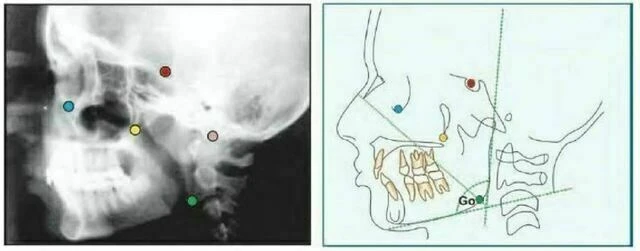

Orbitale (Or) là điểm nằm ở vị trí thấp nhất trên xương ổ mắt. Trên phim cephalogram theo chiều trước sau, mỗi điểm nằm riêng biệt nhau nhưng trên phim cephalogram mặt bên thì đường viền xương ổ mắt trùng nhau. Thông thường, điểm thấp nhất trên đường trung bình của xương ổ mắt được dùng để xác định mặt phẳng Frankfort.

Gonion (Go) là điểm nằm ở vị trí sau nhất và thấp nhất ở góc xương hàm dưới. Nó có thể được xác định bằng cách xem xét thông thường hoặc bằng cách chia đôi góc tạo bởi đường giao nhau của cành đứng và cành ngang xương hàm dưới, cho đường phân giác góc này cắt đường viền xương hàm dưới.

Porion (Po) Đỉnh của ống tai ngoài. Đôi khi do khó xác định porion nên sử dụng đỉnh của bóng thanh tai, điểm này được gọi là “machine porion”

Điểm Xi

Điểm nằm ở trung tâm dạng hình học của cành đứng xương hàm dưới. Vị trí của Xi được xác định thông qua Po – Or (FH) và vuông góc với PT (PTV), cần thực hiện những bước sau:

Mặt phẳng này chứa những tiếp tuyến đi qua các điểm R1, R2, R3, R4 trên các cạnh của cành đứng xương hàm dưới.

Mặt phẳng này tạo thành một hình chữ nhật bao quanh cành đứng xương hàm dưới.

Điểm Xi nằm ở trung tâm của hình chử nhật, trùng với giao điểm của hai đường chéo.